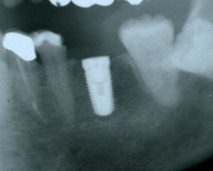

今日のインプラント手術は右上の小臼歯部、大臼歯部に一本づつCamlogインプラントを埋入しました。もちろん大口式、MS式インプラント埋入方法でドリリングはほとんど行わないでできました。この前のNHKのクローズアップ現代でドリリングによるインプラントの危険性を番組でやっていましたが、僕たちのやり方はきわめて安全です。特に上の顎の骨はぼそぼそでドリリングをしてしまうと本当にスカスカになってインプラントを入れて時にゆるゆるで初期固定ができません。そんな時にはMS式オステオトームでジグリングしていくと簡単にさらに横方向ぬ骨を圧縮していきがっちりと入れることができます。世の中で一番怖いこと、それは既成概念と当たり前だと思われていることが実は反対のことだったりします。ダーウインの進化論で絶滅しないで生き残れるのは数が多いものではなく、強いものでもありません。それは機敏に環境の変化にいかに適応できたかどうかということです。ドリリングを過信している先生、恐竜のようにならないでください。

001527_0006_11_02.jpghhh.jpg

001527_0006_11_12.jpgggg.jpg